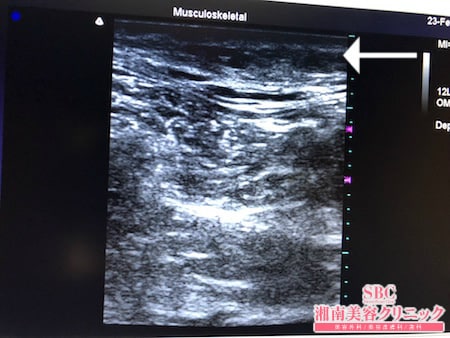

No.252361【脂肪吸引】脂肪吸引は絶対根こそぎ竹田先生!受付スタッフさんの脂肪吸引!右太もも後面術中タッチビュー

では今回は太ももの術中の模様を

見ていきましょう。

いかがでしょうか?

徹底的に根こそぎ!!

ました。